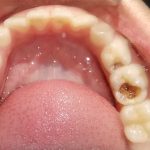

We at the Department of Pediatric & Preventive Dentistry focus on comprehensive oral health care needs of a child from infancy to adulthood and provide comprehensive, therapeutic as well as preventive care to all children including those with special care needs.

Treatment and Services